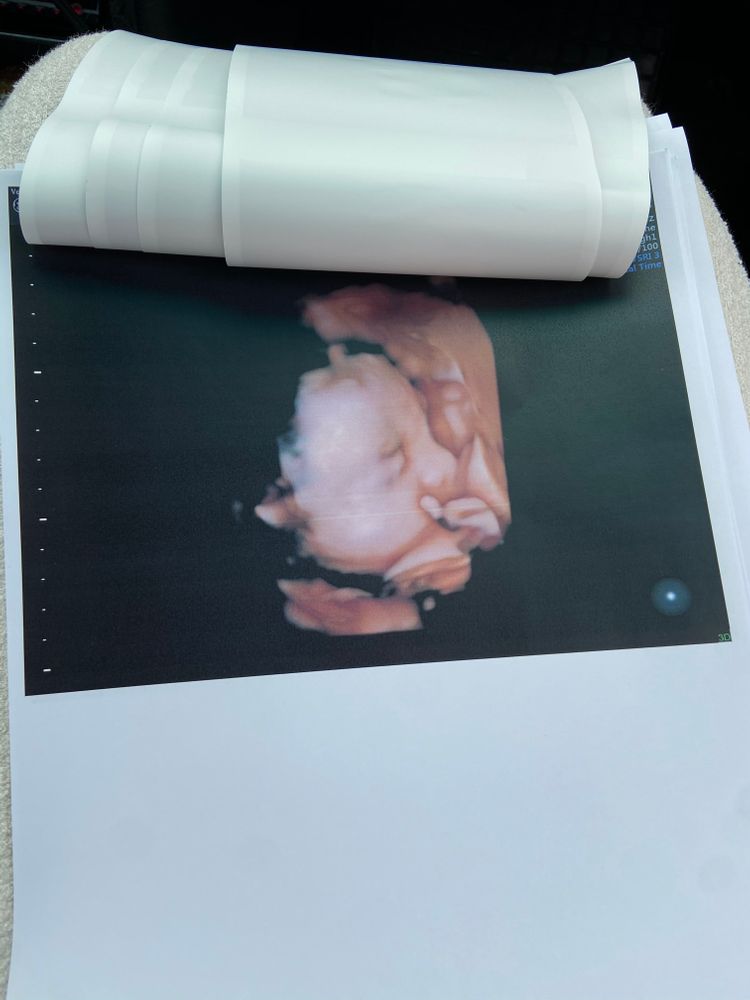

3D УЗИ 28-29 недель Пятых Н.С. "Я здорова"

Сходили с мужем, довольные, хоть и сын лежит в тазовом и вокруг лица руки да ноги. Врач действительно опытная, меня вертели, как шашлык на мангале и паре кадров удалось снять 🤣👌🏻 На счет тазового не парюсь, потому что он еще триста раз изменит позу, места и времени у него вагон и маленькая тележка ☺️ Фоток конечно отдали кипу, с аппарата узи 12 штук и еще в цветной распечатке на принтере 6 штук))

Из веселого: загиб желчного и нос у него в папу, а высокий лоб, длинные ноги и руки , а еще шевелюра с ресницами в меня 😁❤️

Вес 1251г +/- 183г, рост примерно 36-37 см сказали